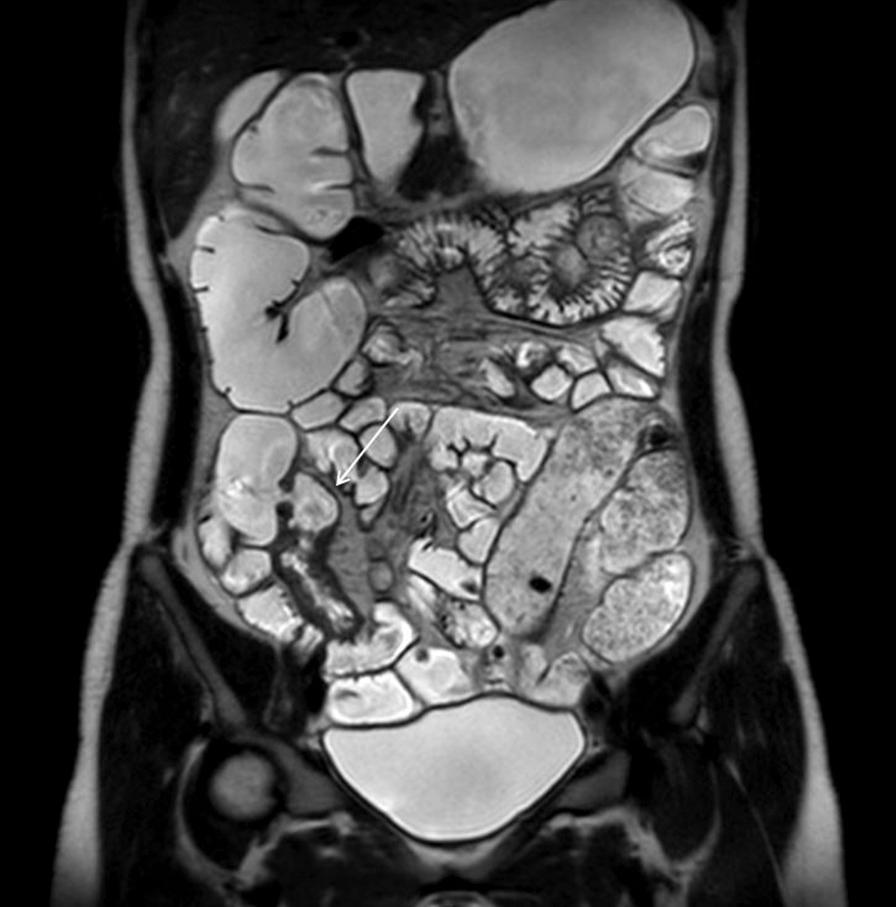

We report the case of an 18-year-old woman with VCD. After treatment with azathioprine 50 mg daily and mesalazine 1 g three times daily, vulvar lesions resolved after 6 weeks. We collected electronic medical data on patient characteristics, and evaluated findings of physical examinations, pelvic MRI, and biopsy specimen obtained from gastroduodenoscopy/colonoscopy.

我们报告了一例 18 岁女性 VCD 病例。在每天使用 50mg 硫唑嘌呤和每天三次 1g 美沙拉嗪治疗后,外阴病变在 6 周后消退。我们收集了患者特征的电子医疗数据,并评估了体格检查、盆腔 MRI 和经胃肠镜/结肠镜获取的活检标本的结果。